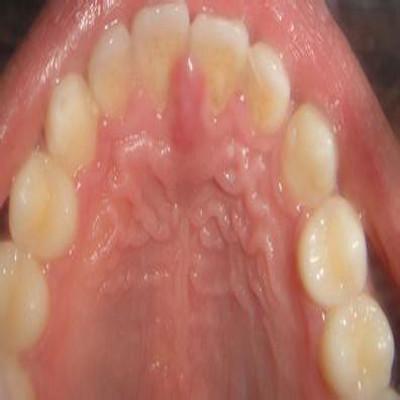

- 口腔内的水疱可能更大,直径可达2-3毫米,因易破而不易被观察到完整形态。

图片清晰地展示了一群聚集在一起的、充满透明液体的水疱,它们位于嘴唇的皮肤上,边界清晰,大小不一,簇状分布是典型特征,如果发生在口腔内,图片可能会显示舌侧或牙龈上有一个或多个半球形、透明或淡黄色的小水疱。